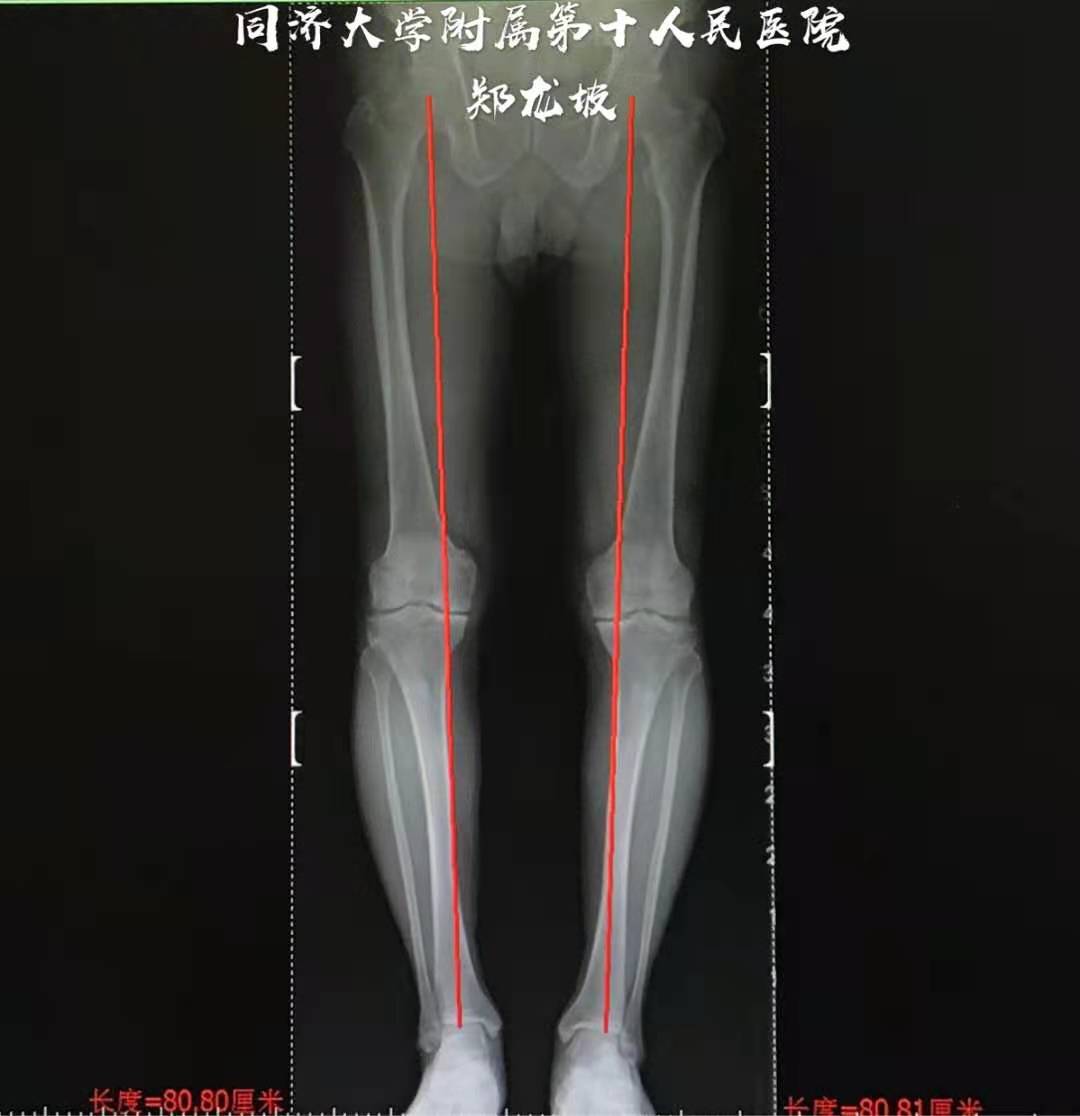

江苏宿迁慕名前来就诊的73岁男性患者,双膝关节骨性关节炎多年,上下楼及下蹲时困难且疼痛加剧,口服多种药物不能缓解症状,经朋友介绍来我专家门诊求诊。检查发现双膝被动屈曲超过90度后疼痛且不不能再屈。X光片显示膝关节内侧间隙变窄,髌股关节软骨磨损,双侧膝关节轻度内翻。

下肢全长片显示双侧膝关节轻度内翻畸形